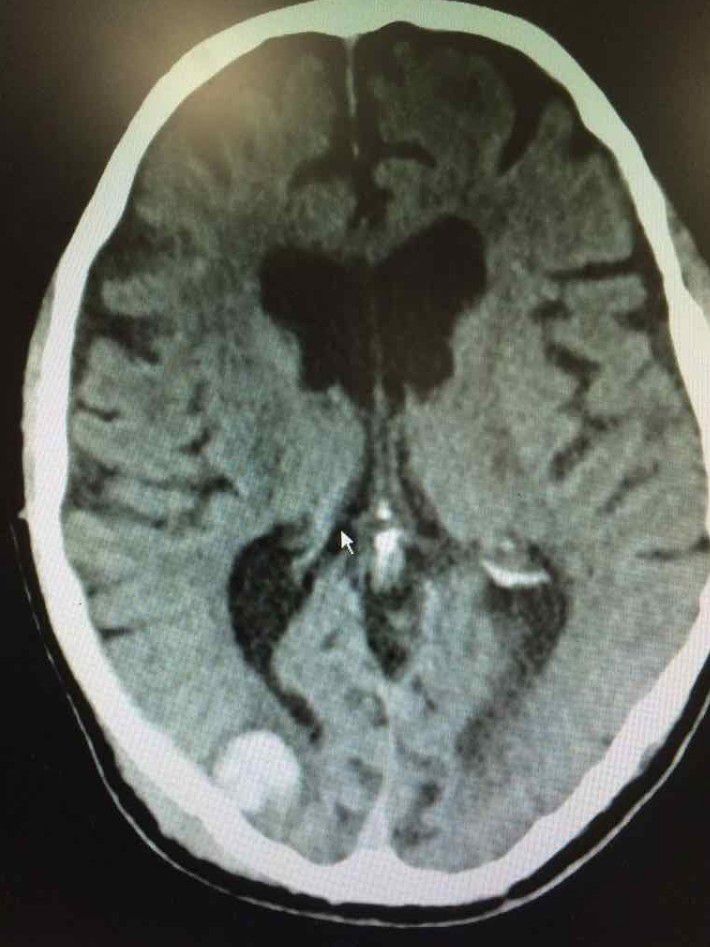

Neurosurgery

Neurosurgeon

Neuro